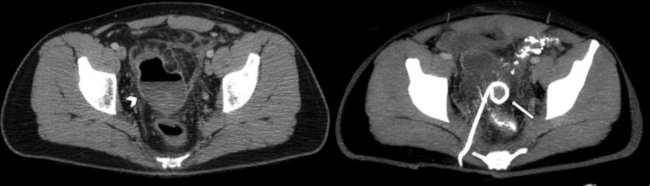

Estadio III: Presencia de líquido libre difuso sin evidencia de neumoperitoneo. Si el paciente está estable sin comorbilidades, se recomienda el lavado laparoscópico y drenaje; en caso contrario, resección quirúrgica con o sin anastomosis (►Fig. 8).

Estadio IV: Presencia de líquido libre difuso asociado a neumoperitoneo. Se recomienda resección quirúrgica con o sin anastomosis (►Fig. 9).